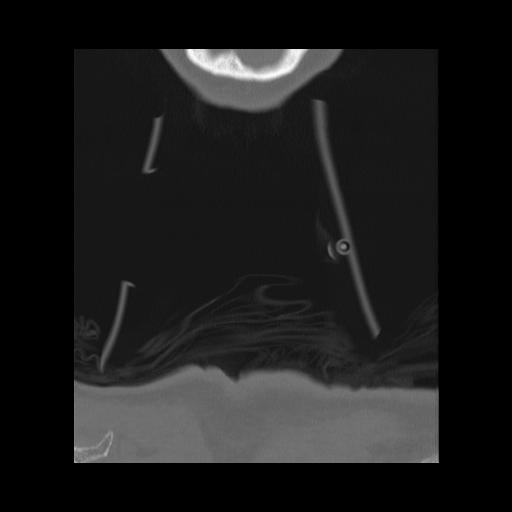

16 HUESO,,Coronal,2.000,HUESO,Coronal,